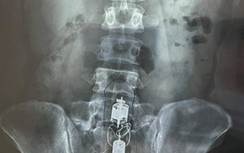

Bác sỹ, Đại tá Cù Xuân Thanh, Chủ nhiệm khoa phẫu thuật lồng ngực - tim mạch cho biết, kết quả chẩn đoán hình ảnh cho thấy bệnh nhân bị cây kéo đâm xuyên thủng khí quản, gây tràn khí màng phổi.

Tại chỗ vị trí hõm ức có vết thương dài 1,5 cm còn dị vật là cây kéo đâm theo hướng từ trên xuống dưới, không thấy máu ở vết thương, chỉ còn lại cán.

Các bác sĩ đã xử trí phẫu thuật cấp cứu, phát hiện dị vật làm rách mặt trước khí quản 0,5 cm, đường đi của mũi kéo lướt mặt sau và dưới của tĩnh mạch cảnh trên, xử trí tổn thương... và rút được dị vật.